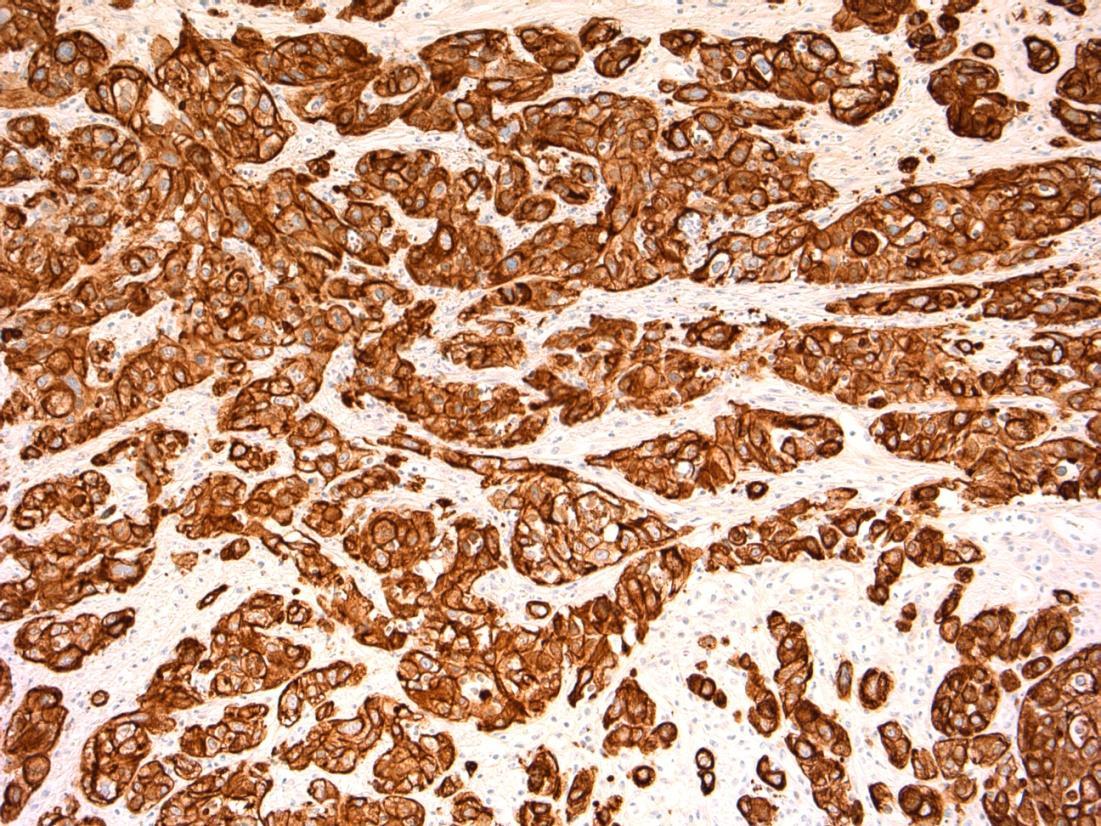

64F. Incidental imaging finding of nodule measuring 4cm in segment 2 of liver ? HCC.

Liver lobe resection received.

Case

14 •

Liver - angiomyolipoma

14

HMB45 CD117 AE1/3 SMA

Liver Description: Liver containing well circumscribed spindle cell tumour with 3 components – smooth muscle cells (predominant), adipose tissue and blood vessels. Diagnosis: angiomyolipoma Differential Diagnosis: Leiomyoma (usually no prominent vascular or adipose component, negative for HMB45) GIST (CD117+) Mets of sarcoma / spindle cell carcinoma – more atypia Plan: IHC: SMA+, HMB45+, CD117-, AE1/3+ Correlate with clinical history ? Tuberous sclerosis etc Comments: • Liver is 2nd commonest site after kidney • Often detected incidentally, usually benign • May be sporadic but is associated with tuberous

and with TSC2 / PKD1 contiguous gene

(especially if

AML

sclerosis

syndrome

bilateral/multifocal).

3.5 Clinical features, associations 3.0 Differential diagnosis and use of IHC 2.5 Description with diagnosis or DD including AML 2.0 Differential diagnosis with mention of AML but favouring other diagnosis 1.5 Differential diagnosis with no mention of AML or a benign diagnosis 1.0 Malignant diagnosis Case 14